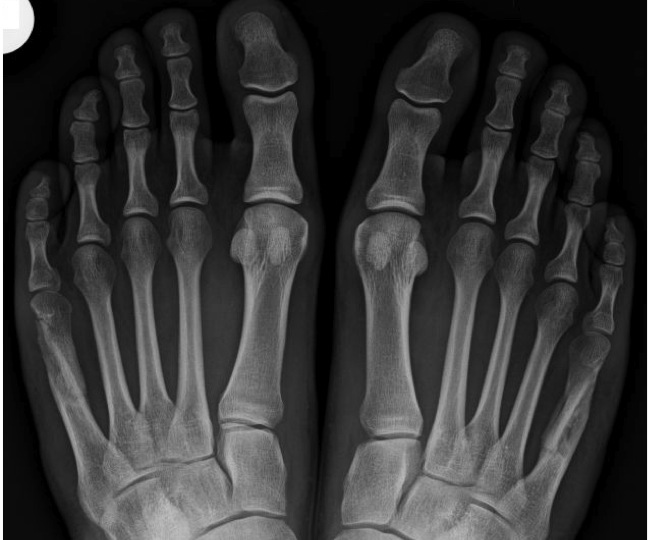

Se définit comme une instabilité et un conflit sur la cinquième tête métatarso-phalangienne et donc l’équivalent en miroir de l’hallux valgus, mais située sur le bord externe du pied.

Ils sont dus aux frottements et / ou la surcharge mécanique qui provoquent une inflammation ou des durillons sur le bord externe du cinquième métatarsien.